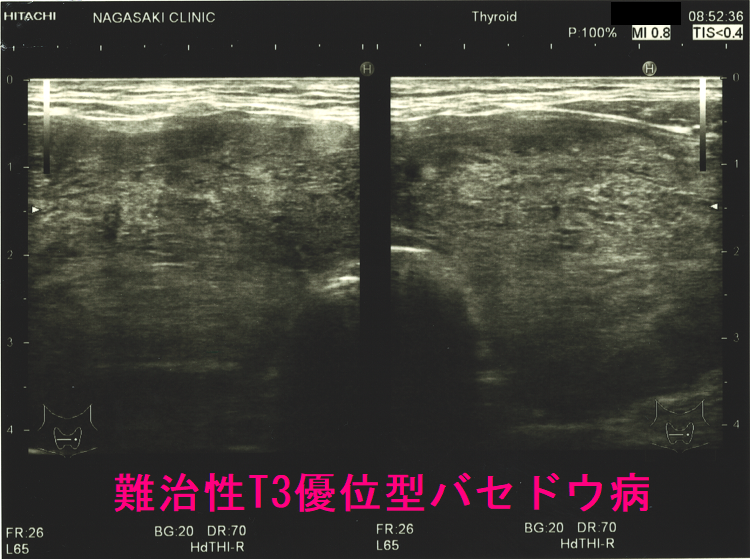

T3優位型バセドウ病の超音波(エコー)所見

ケース② 巨大甲状腺腫・甲状腺内部血流増大

ケース③ 異常に太い下甲状腺動脈